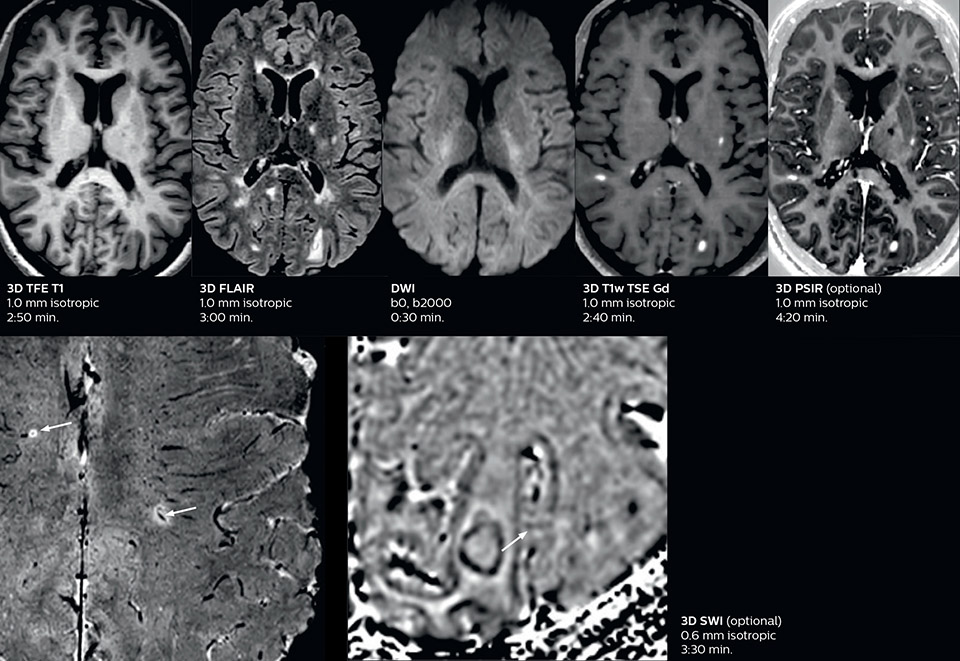

The abbreviated MS protocol for brain is only around 9 minutes, so in case of suspected multiple sclerosis, one or two more advanced sequences may be added, such as PSIR (phase sensitive inversion recovery) or susceptibility-weighted sequences to help us make more confident diagnoses in these inflammatory cases.

In this example, the optional 3D multishot susceptibility weighted sequence with 0.6 mm isotropic voxels is 2 lesions with a central vein sign (arrows) and one lesion with a phase-rim sign (arrowhead). The total scan time, including SmartBrain and axial PD/T2 3mm, is 11:10 min. and is 18:30 min. with the optional 3D PSIR and 3D SWI multishot included.

“We used to have long examination times for certain types of patients, a few lasting more than 40 minutes,” says Dr. Savatovsky. “What is remarkable, is that now all these examinations are below 30 minutes, which opens up opportunity to add more sequences when needed. It’s really hard to keep a patient for more than 40 minutes in the scanner, but because we have now cut scan times by at least 10 minutes, we can add more sequences without making the exam too long. And this is where the new system helps us make a difference. Examples include our examinations for informing brain tumor classification or giant cell arteritis workup, or for intracranial wall imaging – so in patients where we need several advanced sequences or high resolution sequences.” “We added three additional sequences in our brain neoplasm classification exam: a 3D SWI sequence, APT and ASL on top of 3D morphologic sequences, an isotropic DSC (dynamic susceptibility contrast) and multivoxel spectroscopy. I think that in patients that need a classification for brain mass, for example, we can provide a more detailed and confident diagnosis than before, allowing the clinicians to decide for either a medical workup if no tumor is suspected, or for neurosurgery as soon as possible if a neoplasm is suspected.” “In multiple sclerosis patients, we increasingly include a multishot susceptibility sequence [3] in our routine cases, thanks to the shorter scan times. Our abbreviated MS protocol for brain is around 8 to 9 minutes, so we can ask for one or two additional sequences to visualize the central veins, or to get an additional contrast to better depict posterior fossa lesions. In cases of white matter lesions of unknown significance on FLAIR images, for example when we see high signal hyperintensities in the brain, we can add on more advanced sequences such as PSIR (phase sensitive inversion recovery) or susceptibility-weighted sequences to help us in distinguishing between MS and nonspecific or vascular abnormalities in these inflammatory cases.”